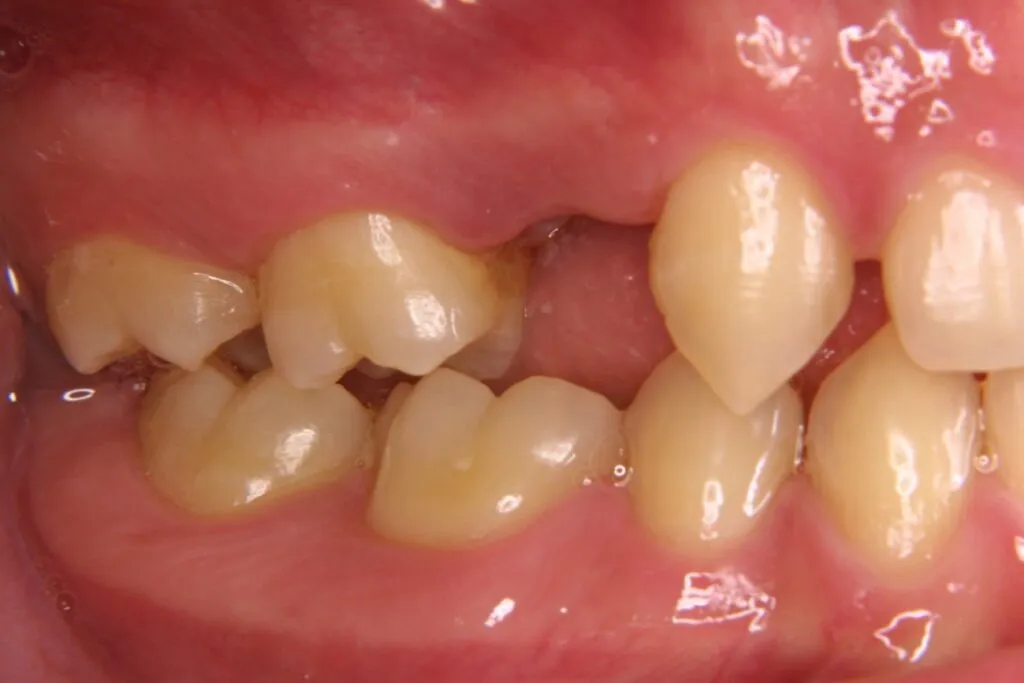

症例⑦

| 主訴 | 残根状態 歯を入れたい |

|---|---|

| 診断名 | 咀嚼障害 |

| 年齢 | 29歳 |

治療に用いた装置(治療法) | インプラント |

| 部位 | 左上6・左上7・左下6・左下7 |

| 治療期間 | 8か月 |

| 治療費用 | 1,848,000円 |

| リスク・副作用(治療に関する) | 腫脹、しびれ |